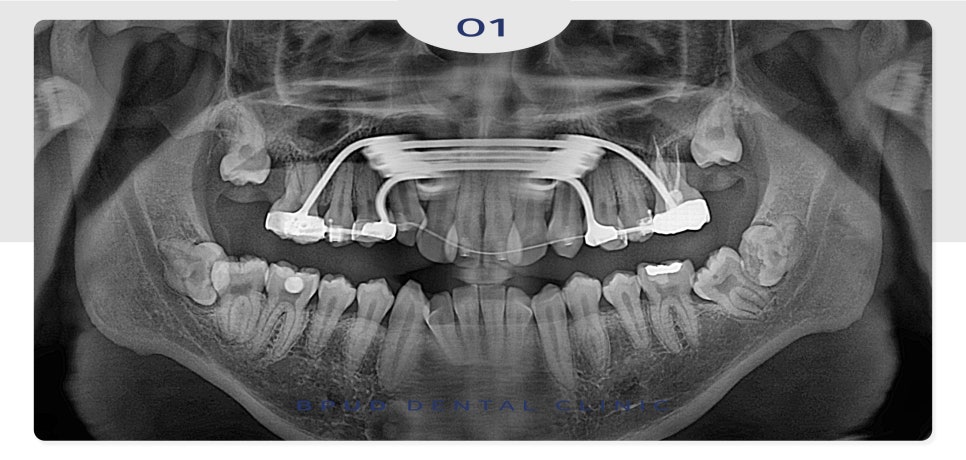

23.05.31

악궁이 작아서 치아 교정을 진행 중이신

상태로 사랑니 또한 완전히 매복되어 있었고

앞쪽 치아에 걸려 난이도가

매우 높은 케이스였는데요.